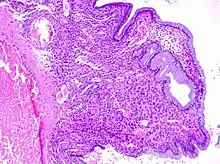

Cervical polyps can be seen during a pelvic examination as red or purple projections from the cervical canal.[4] Diagnosis can be confirmed by a cervical biopsy which will reveal the nature of the cells present.[4]

Structure

Cervical polyps are finger-like growths, generally less than 1 cm in diameter.[4][5] They are generally bright red in colour, with a spongy texture.[3] They may be attached to the cervix by a stalk (pedunculated) and occasionally prolapse into the vagina where they can be mistaken for endometrial polyps or submucosal fibroids.[5]